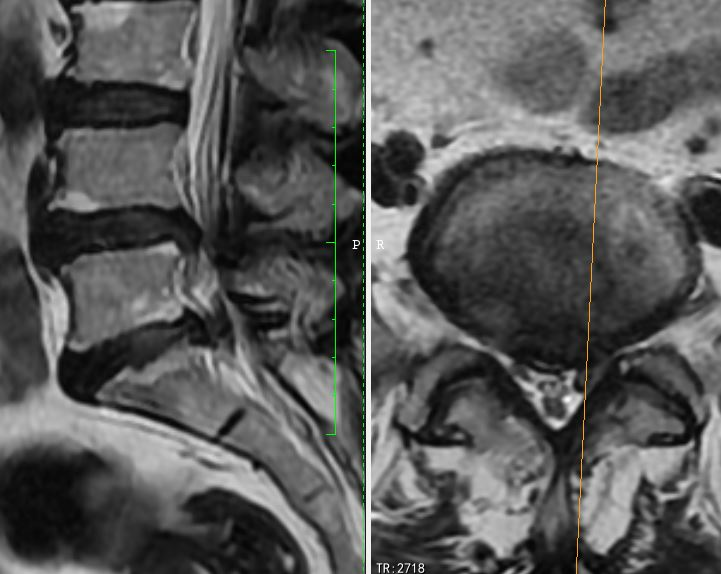

以下是我们查体资料展示:

我们治疗组将家属的顾虑和要求汇报于张宏主任,张宏主任详细阅片、细致查体后认同治疗组的治疗方案,耐心的向家属再次讲述了治疗方案和治疗的必要性。